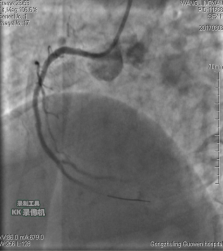

中日聯(lián)誼閆明洲教授向家屬交代病情及介入相關(guān)并發(fā)癥后,患者及家屬同意冠脈支架治療,過程順利,于右冠脈中段植入Firebird2 2.5*33mm 藥物洗脫支架1枚。

術(shù)前 術(shù)后

患者冠脈支架植入術(shù)后,胸骨后疼痛癥狀明顯好轉(zhuǎn),復(fù)查心電圖抬高的ST段回降。